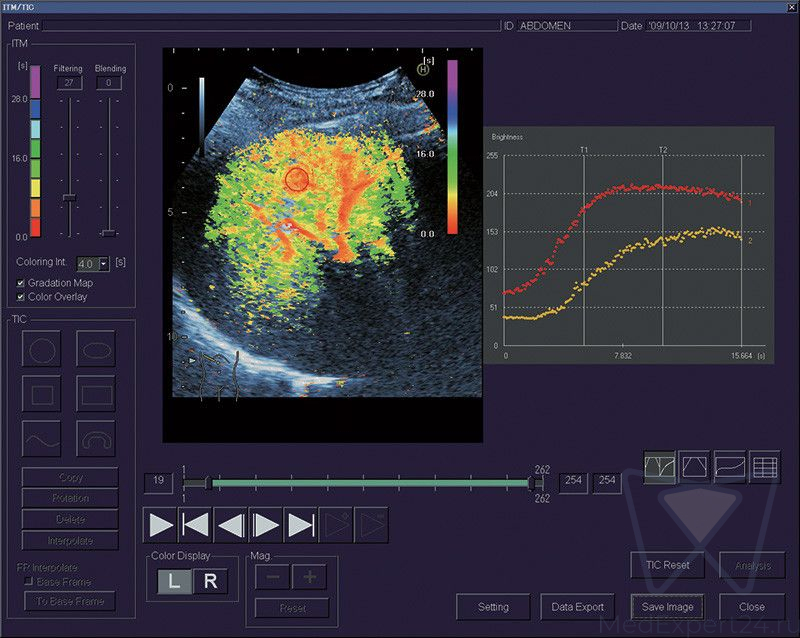

Ультразвуковая система HI VISION Ascendus является кульминацией длительного сотрудничества большой сети исследовательских лабораторий корпорации Hitachi. Благодаря усердной работе опытных профессионалов, стало возможным воплотить самые передовые технологии в УЗИ аппарате экспертного класса.

Расширенные возможности визуализации:

- HI-RTE эластография в режиме реального времени,